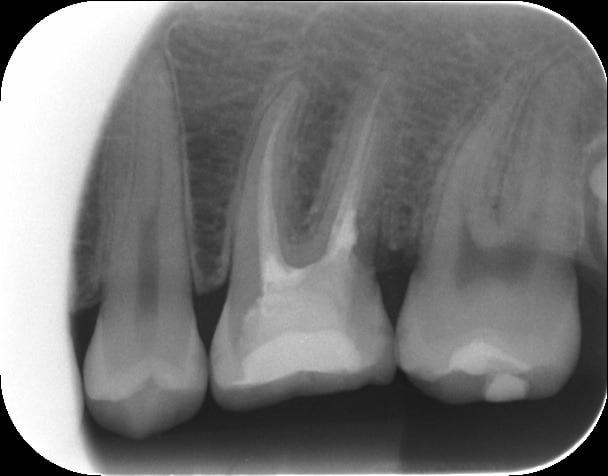

Patiente de 19 ans venue en urgence pour des douleurs type pulpite.

3 mois plus tôt, son dentiste a réalisé un compo sur la 46. A la radio, je suppute que sous le compo il a mis une protection pulpaire (?), mais c'est surtout l'image en distal qui m'interpelle! Est-ce bien une résorption interne???

Après discussion avec la patiente, je décide d'ouvrir la dent pour voir sur quoi je tombe.

Prend une rétro avec deux forte angulation différente la prochaine fois si tu peux.

Il y a une possibilité que ce soit un artéfact de la radio. La 6 semble avoir une racine distal bifide, au niveau de la zone de séparation si tu est dans un axe qui sépare légérement les racines l'une de l'autre ça peut apparaître peut radio dense, tu as le même type d'image au 1/3 apical de la 5. Mais la séparation peut aussi se produire beaucoup plus haut et les racine revenir ensuite dans le même axe. Ce n'est pas courant mais ça expliquerait ton image et pourquoi ça n'as pas saigné quand tu as ouvert.

Une abération anatomique est aussi plus probable qu'un résorption interne.

D'après the pathways of the pulp (ulta abrègè).

Le diagnotique différentiel se fait en prenant la radio sous différent angle.

Si c'est interne tu peux le prendre sous n'importe quel angle la lésion restera toujours associé au canal (normal c'est l'orgine de la lésion); De plus tu dois toujours avoir une lésion bien délimitée. (trou au milieux de la racine qui est l'élément le plus radio dense)

Si c'est externe quand tu fais varier l'angulation, la lésion doit s'éloigné de la pulpe (normal elle commence à l'interface zone racine) les zone ne sont pas toujours nette (lésion du a un process inflamatoire avec des limites osseuse et dentinaire, différente densité radiologique, donc suivant l'angle sa varie). En faisant varié l'angulation tu dois étre capable de déterminer la position de la lésion

Donc d'après ta radio de mémoire c'est plutôt externe, le problème étant que les résorption externe sont moins fréquente que les internes.